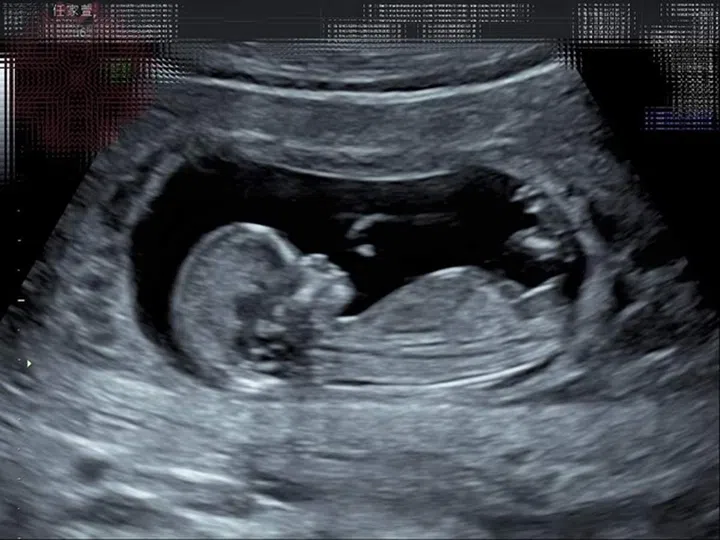

无论顺境或逆境,坦然接受人生赐予你的礼物。Selina 3月13日透过Podcast节目《迎任而解》宣布怀孕喜讯。目前怀孕12周,她直言感受到人生中不可思议的美好时刻,第一次听到宝宝心跳时,更开心得暴哭!Selina因为长有4颗子宫肌瘤,因此没想过自己可以在41岁的时候自然受孕,虽然孕期害喜症状多,但完全不影响她对小生命的期待:“再怎样的过程,我都觉得整个人充满著希望,这个生命很妙,他不只有自己的生命,他又给与我另一个生命,我有一种无与伦比的自信跟骄傲。”她在IG配上超音波照及妈妈手册,从文字和照片让人感受到她满满的喜悦,让老粉丝都忍不住泪目:“Selina要一直快乐幸福下去!”